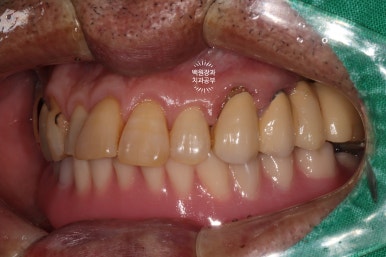

측면 사진에서도 상당히 깔끔하게 제작된 임플란트를 보실 수 있습니다!!!

위턱 교합면 사진입니다.

오른쪽의 까만색으로 보이는 부위들은 교합조정을 위한 교합종이의 색깔입니다.

충분히 깔끔한 모양새고...

이가 없던 부위는 이가 생겼으니 가장 큰 변화를 이루어냈다고 생각해야겠네요.